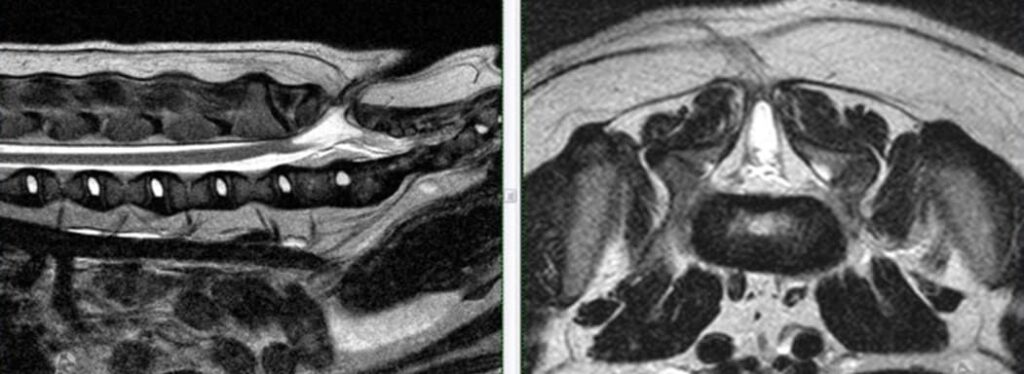

Η μαγνητική τομογραφία (MRI) είναι πιο ευαίσθητη στον εντοπισμό σχετιζόμενων ανωμαλιών των μαλακών μορίων, όπως μηνιγγοκήλης ή μηνιγγομυελοκήλης.

Οβελιαίες και εγκάρσιες Τ2-ακολουθίες στο επίπεδο του μεσοσπονδύλιου διαστήματος Ο7–Ι1 νεαρού English Bulldog με δισχιδή ράχη.